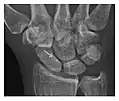

Occult osseous injuries may result from a direct blow to the bone by compressive forces of adjacent bones against one another or by traction forces during an avulsion injury. Lesions in the tibial plateau, hip, ankle, and wrist are often missed. In a tibial plateau fracture, any disruption of the posterior and anterior cortical rims of the plateau should be sought. Impaction of subchondral bone will appear as an increased sclerosis of the subchondral bone (Figure 1). In the hip, posterior acetabular fractures also present subtle radiographic findings. The acetabular lines should then be carefully examined keeping in mind that the posterior rim, which is harder to see on X-rays, is more frequently fractured than the anterior rim (Figure 2). In the wrist, detection of carpal bone fractures is often challenging, with up to 18% of scaphoid fractures radiographically occult. Carpal fractures, especially the scaphoid, are associated with the risk of avascular necrosis. In apparently normal wrist radiographs from symptomatic patients, if there is history of a fall on an outstretched hand with pain in the anatomic snuffbox, suggesting scaphoid injury, the initial examination with posteroanterior, lateral, and pronation oblique views must be complemented by other specific views such as supination oblique and the "scaphoid" view A careful examination of cortices for evidence of discontinuity or offset and cancellous bone for lucency is necessary (Figure 3).[1]

Figure 3: A 26-year-old man presenting with wrist pain after being assaulted. (a) Initial anteroposterior radiograph shows a subtle linear lucency within the scaphoid extending to the scaphocapitate articular surface that was overlooked (arrow). (b) Initial "scaphoid" view was negative. (c) Followup anteroposterior radiographs, 12 days later, shows obvious scaphoid fracture (arrows).[1]